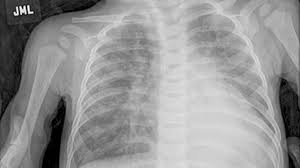

The Stages Of Pulmonary Sarcoidosis What Do They Really Mean Foundation For Sarcoidosis Research from www.stopsarcoidosis.org Emphysema does not, however, lead to lung cancer. In the united states, trends in lung cancer tend to follow trends in cigarette smoking. Lung cancer develops due to the overgrowth of. Chronic obstructive pulmonary disease (copd) is a serious lung condition found mostly in smokers. If the condition is misdiagnosed or its symptoms are ignored, a patient may not receive appropriate treatment until the cancer has progressed to an advanced stage. When sarcoidosis affects the lungs, symptoms can mimic idiopathic pulmonary fibrosis including shortness of breath and a dry cough. Pneumonia is a lung infection that leads to breathing difficulties and fluid in the lungs. Malignant tumors trigger inflammation in surrounding normal lung tissue, and they may obstruct your airways and interfere with normal airflow.

Stereotactic Body Radiation Therapy For Early Stage Non Small Cell Lung Cancer A Primer For Radiologists Radiographics from pubs.rsna.org Having copd may put you at risk for lung cancer and heart disease, among other conditions. This is because smoking complications can extend from lung tissue damage (emphysema) to lung cell damage (cancer). When cancer begins in the cells of the lung it is known as primary lung cancer. Various viruses, bacteria, and fungi can cause pneumonia. Lung cancer is a general term that includes all abnormal lung tissue cells that multiply unregulated and form tumors or growths in the lungs.these tumor cells may spread (metastasize) to other parts of the body.; In lung cancer, lung cells exhibit abnormal and uncontrolled growth starting the lungs, while asthma is caused by inflammation and/or mucus that decreases or blocks the breathing passages (bronchioles) of the lungs. Although slipping from emphysema to copd is usually not a drastic decline in health, early detection of lung cancer is critical for increasing your treatment options and improving your prognosis. Initial reports of an association between lung cancer and emphysema date back to the 1950s, when a report on 10 patients with congenital cystic pulmonary emphysema who died from primary lung cancer was published (4).